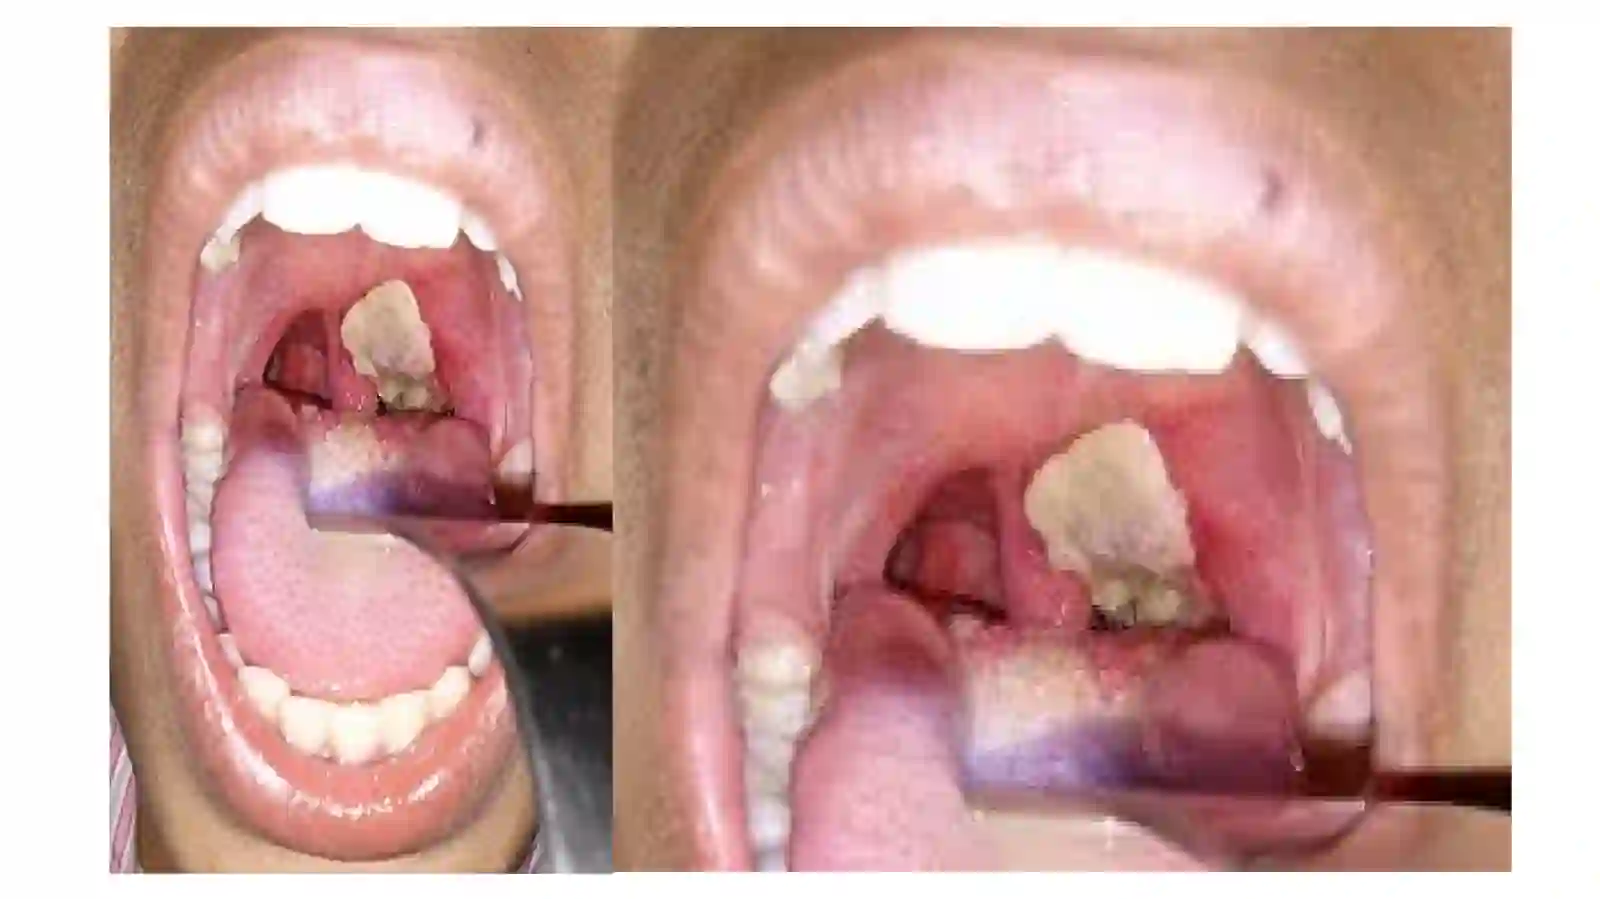

Difteriya,ko’ky’o’tal,epidemik parotitdabolavauningoilasigahamshiralikparvarishi